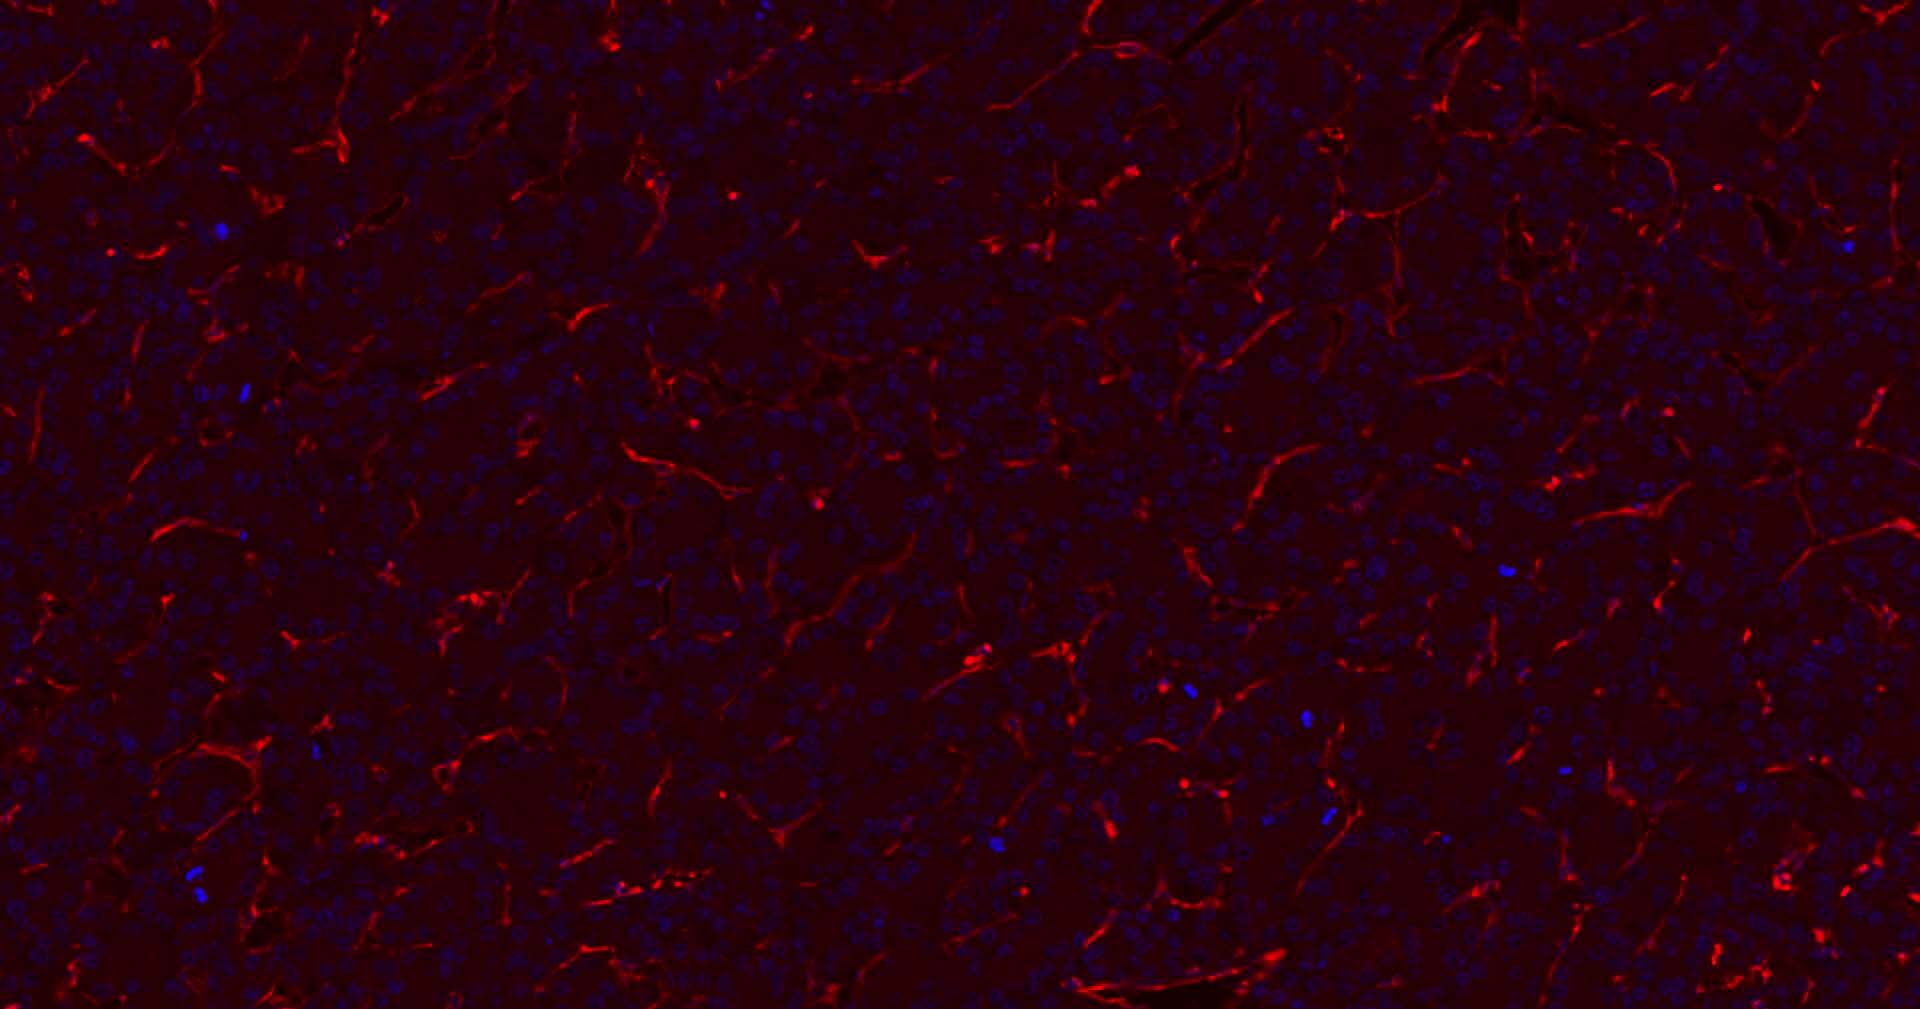

Paraformaldehyde-fixed, paraffin embedded Human Liver ; Antigen retrieval by boiling in sodium citrate buffer (pH6.0) for 15 min; Antibody incubation with CD31 Monoclonal Antibody, Unconjugated (bsm-10825M) at 1:200 overnight at 4°C. Followed by conjugated Goat Anti-Rabbit IgG antibody (Red, bs-0296G-BF594), DAPI (blue, C02-04002) was used to stain the cell nuclei.